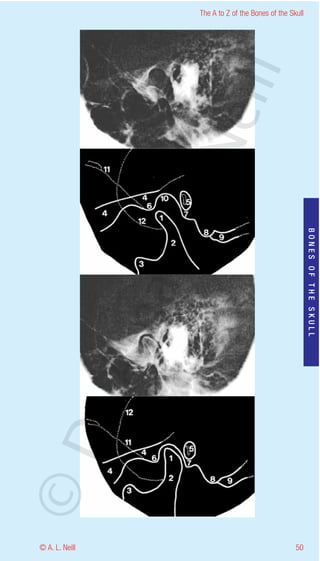

The A to Z of the Bones of the Skull

Mandibular joint

eill

Temporo-Mandibular joint (TMJ) Lateral

radiology

Open - upper

Shut - lower

aN

1      Head of mandible – Condylar process

2      Neck of the Mandible

3      Coronoid process

4      Zygomatic arch

5      External auditory meatus + Handle of the malleus

6      Articular cubicle

nd

BONES OF THE SKULL

7      Tympanic plate

8      Mastoid process

9      Groove for posterior belly of Digastric muscle

10     Mandibular fossa

ma

11     Greater wing of the sphenoid (basal surface)

12     Lesser wing of the sphenoid

rA

©D

49                                                       © A. L. Neill